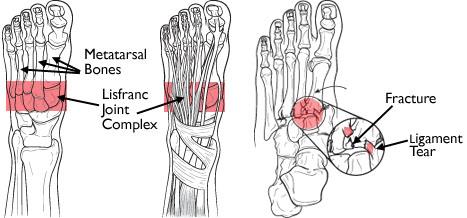

Комплекс сочленений Лисфранка

• Неправильное выравнивание второго предплюсневого сустава — общая черта переломов-вывихов Лисфранка. На передне-заднем виде рентгена виден латеральный сдвиг основания второй плюсневой кости и диастазис более 2 мм между основаниями первой и второй плюсневой костей. Рекомендуется сделать рентген в весовом положении, чтобы поврежденная сторона могла быть сравнена с противоположной стороной.[3]